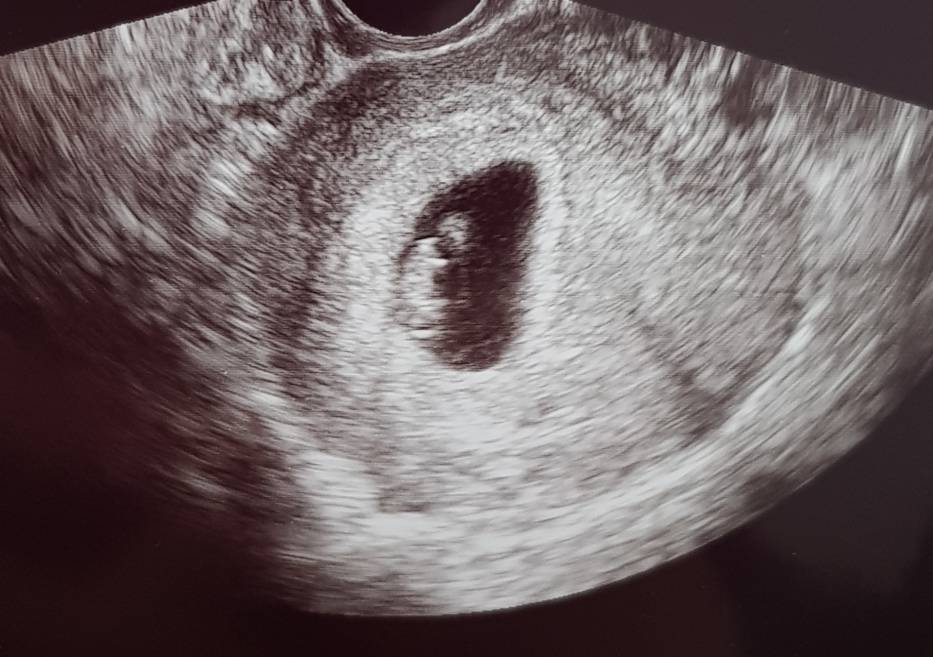

Ale! Jestem po wizycie. Wsyztsko jest ok Z serce bije :) nie słyszałam, ale widziałam. Dzidzi ma 120mm, dostałam skierowanie na badania i na następnej wizycie z wynikami założą mi kartę ciąży :) om 7+5, usg 7+3 termin na 18.01 odetchnęłam :)

20200608_115326.jpeg